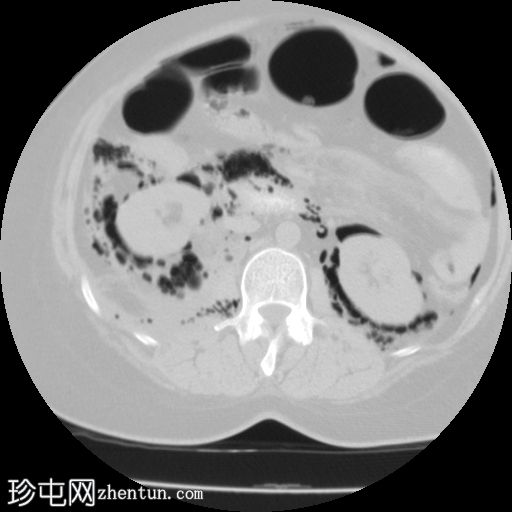

2.png

冠状位

食管下三分之一处管壁均匀增厚,可见气泡(穿孔起始部位),纵隔及双侧胸膜腔内可见游离气体,提示食管穿孔。

十二指肠内可见造影剂早期渗漏至十二指肠旁间隙(第二个穿孔部位),同时主动脉旁、结肠旁、肾周及膈下区域可见游离气体,提示十二指肠穿孔。